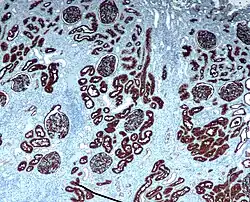

Иммуногистохимические окрашивания

Иммуногистохимия (ИГХ) — это метод, который позволяет выявить точную локализацию того или иного антигена благодаря связыванию его с мечеными антителами (реакция антиген — антитело). Применяется дополнительно к классическим методам окрашивания для постановки более точной постановки диагноза и назначения лечения, а также для выявления опухолей, инфекционных заболеваний[19].

Локализация антигена в гистологическом препарате определяется с помощью прямого и непрямого метода иммуногистохимической реакции.

Прямой метод иммуногистохимической окраски основан на использовании меченых антител, которые непосредственно связываются с искомым антигеном. Недостатком прямого метода является слабая интенсивность окраски. Повысить чувствительность можно с использованием непрямого метода иммуногистохимической окраски, который использует меченные вторичные антитела, непосредственно взаимодействующих с первичным антителом после его связывания с антигеном[20].

Наиболее широко распространено непрямое иммуноокрашивание с использованием биотинавидинового комплекса. Биотин (витамин H) стоек к высоким температурам, к кислой и щелочной среде, а также хорошо растворим в воде и спирте, является коферментом во многих реакциях присоединения. Биотин легко вступает в стойкое соединение с различными белками, в том числе с ферментами и иммуноглобулинами. Биотин образует с авидином чрезвычайно стойкий комплекс.